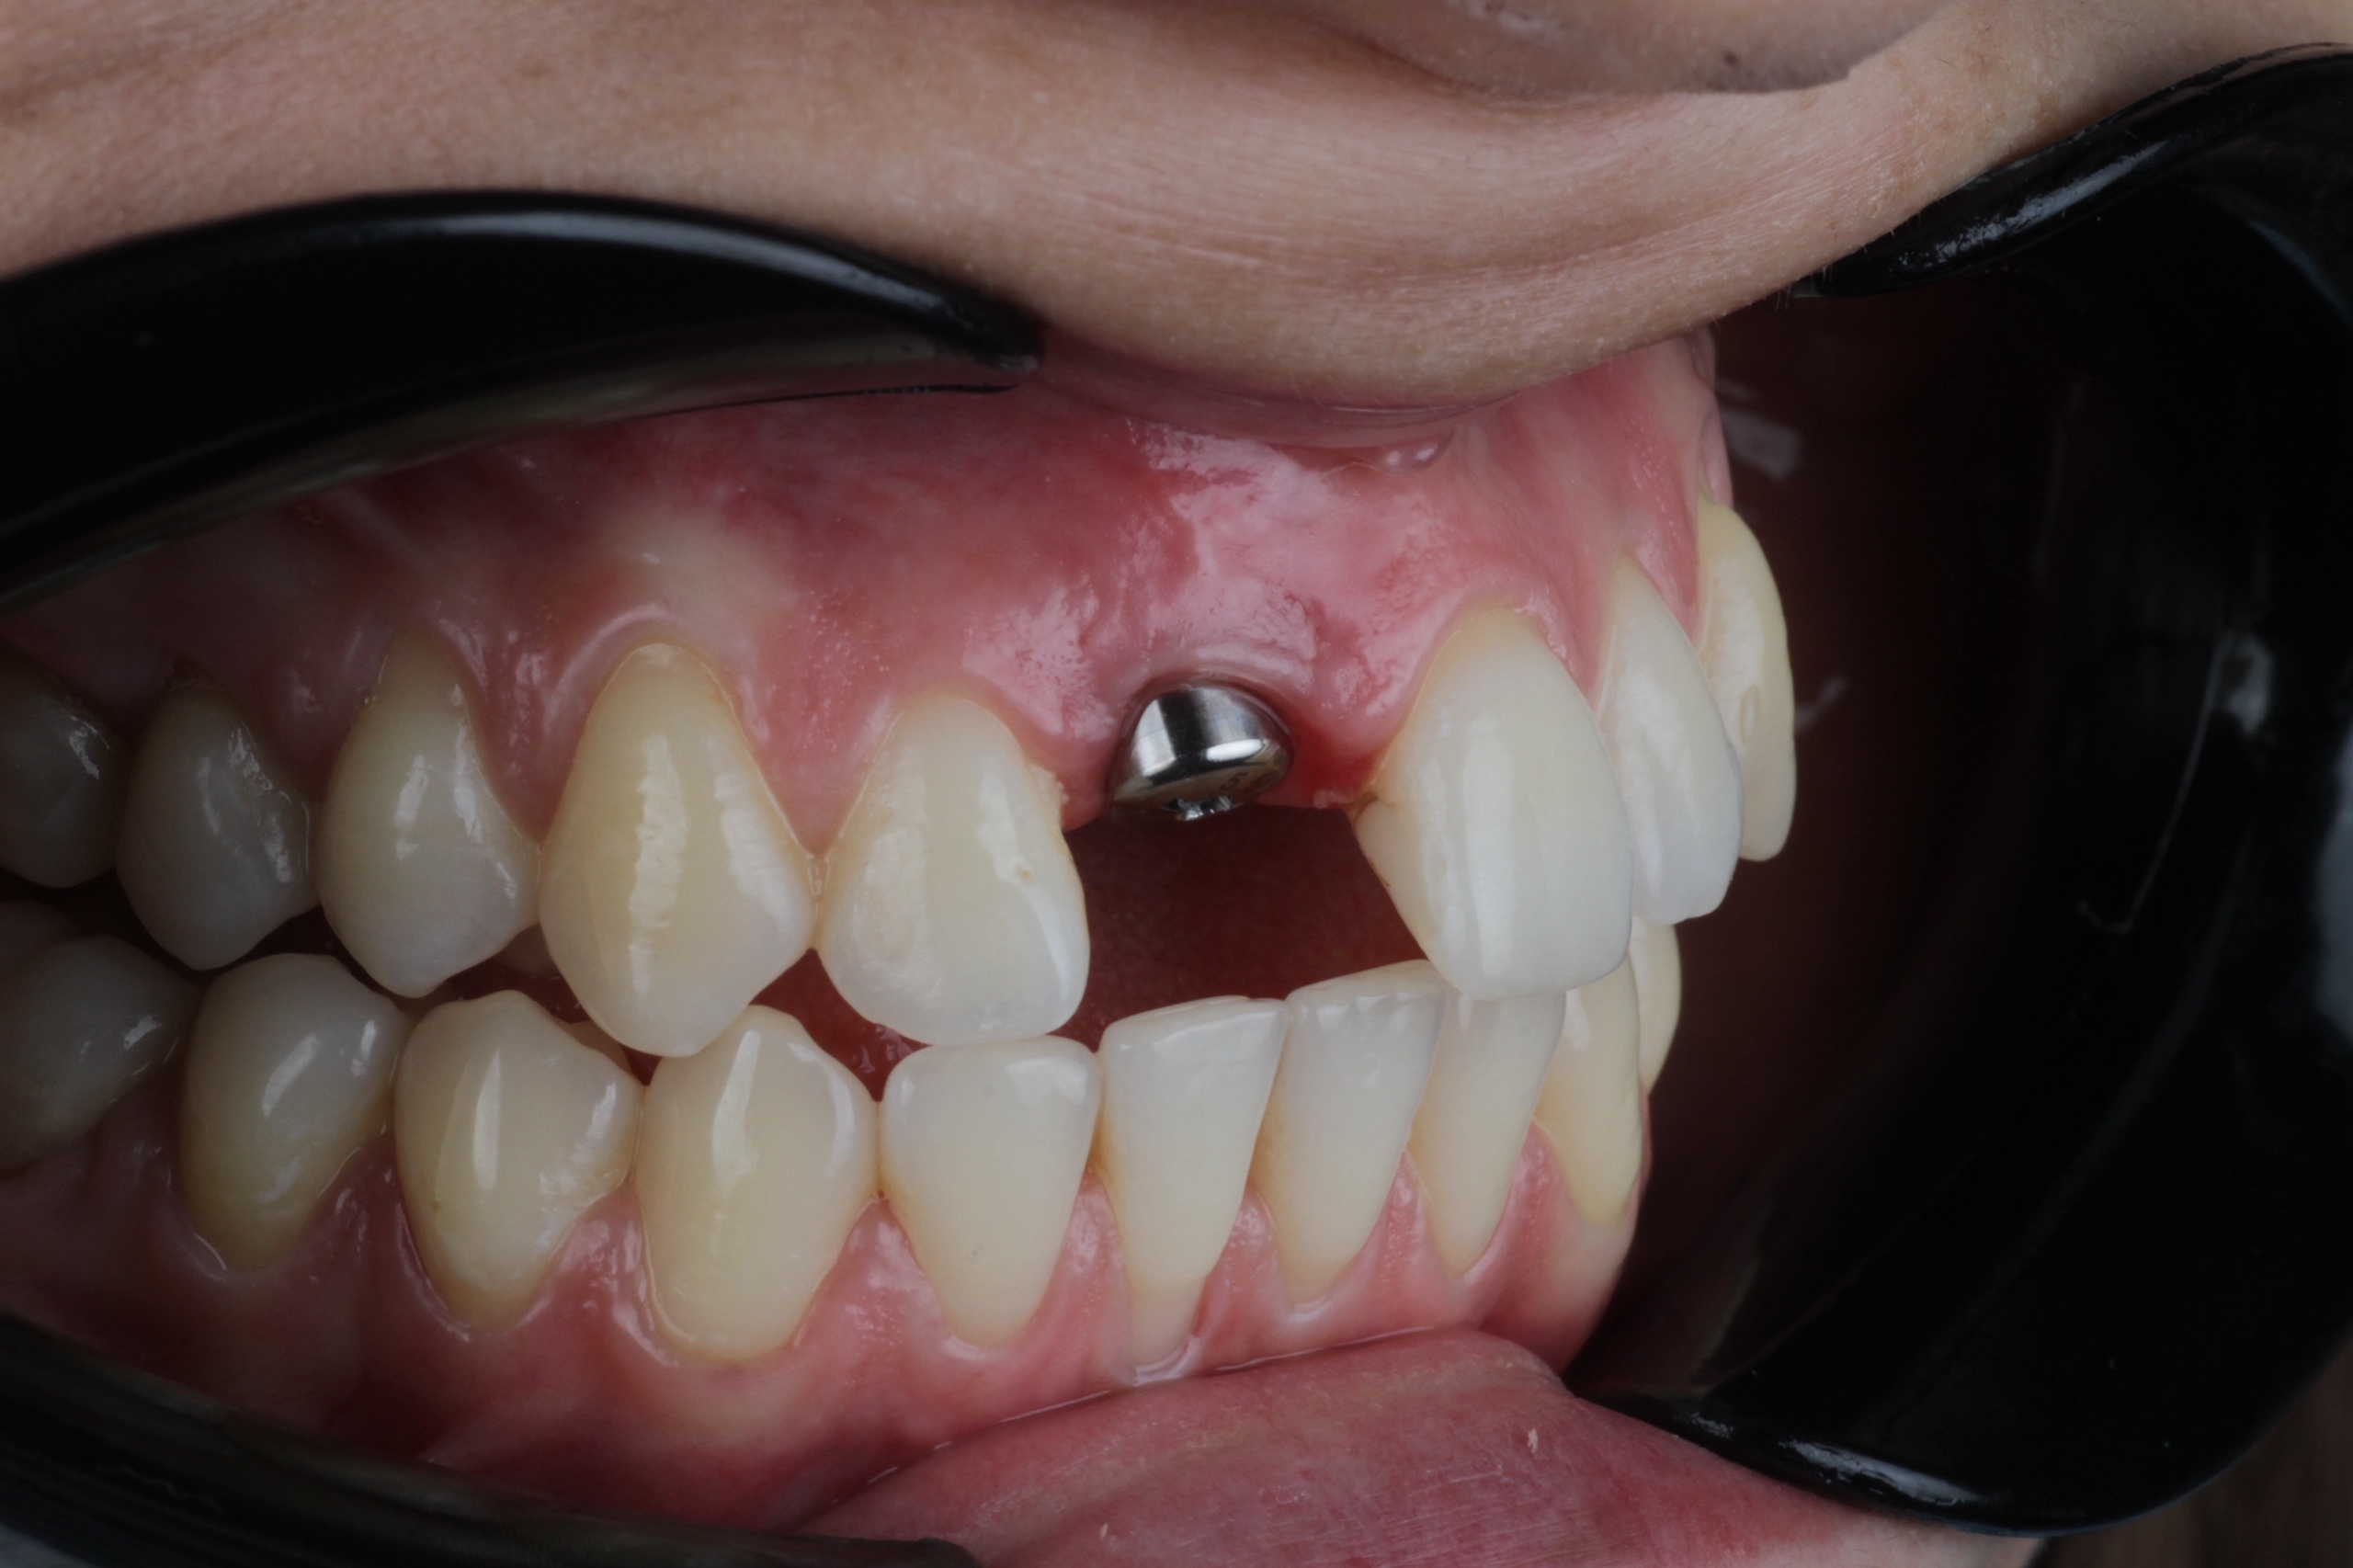

Одномоментно – имплант устанавливают сразу после удаления разрушенного корня в одно посещение;

Имплантация

От 32 500 Имплантация фото